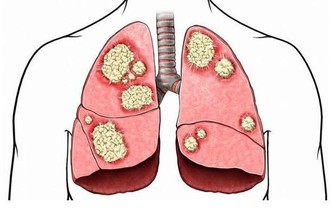

1.肺癌和肝癌

症狀一:五年不發燒

這種人小心肝癌和肺癌。不發燒,好像身體很好,其實是免疫力太差了,身體機能下降了,對致病的因素沒反應了。

症狀二:夜裡老是醒

夜裡1點到3點老醒的小心肝癌,3點到5點老醒的小心肺癌,這一般會發生在查出來的2到3年前!